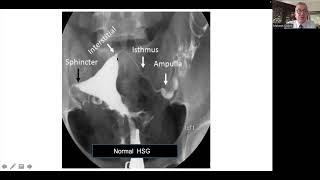

Hangi Organ Için Hangi Tetkik Yapılmalı?